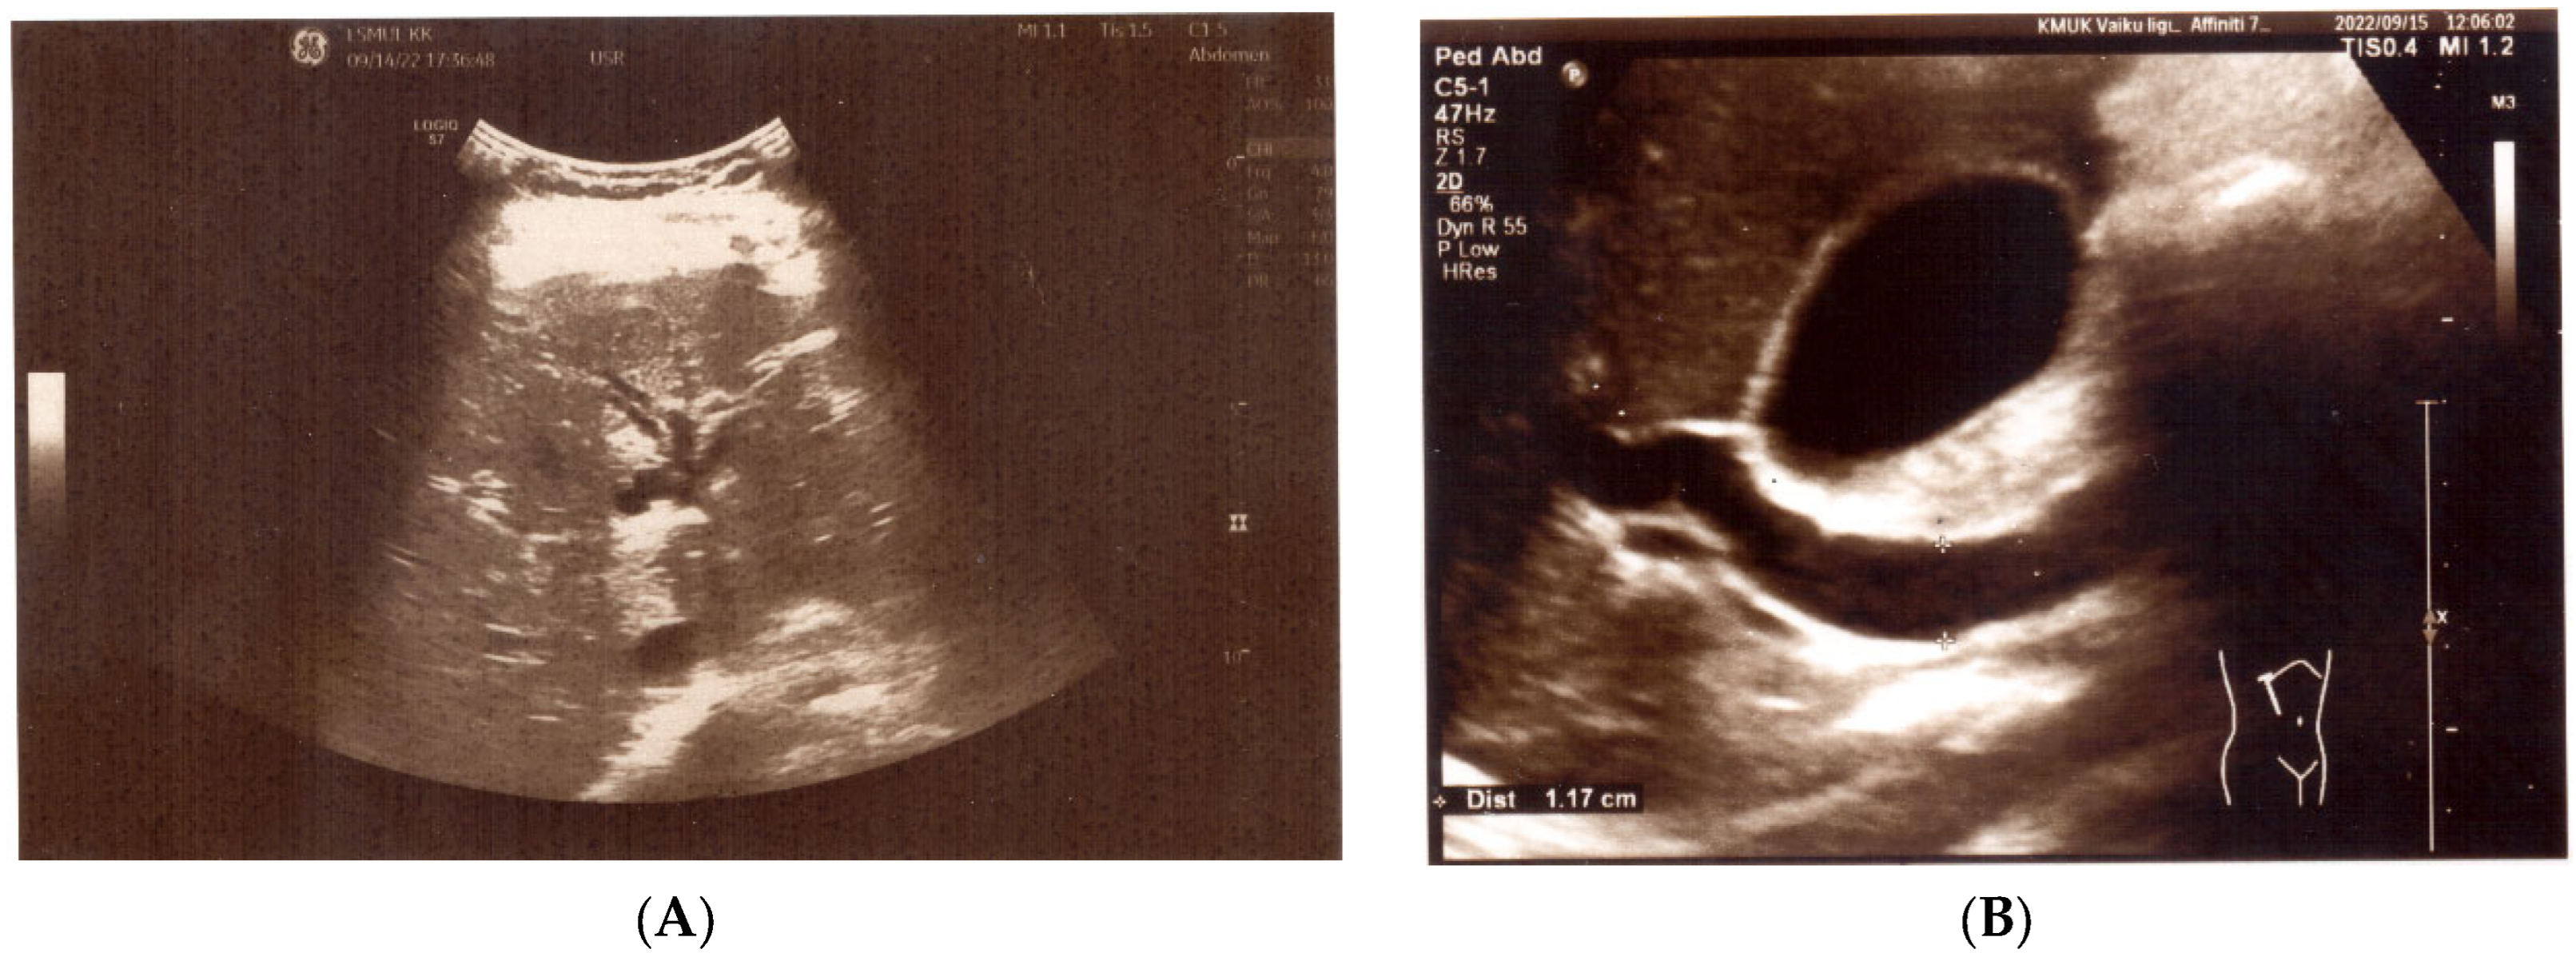

The patient then underwent helminth testing at an outpatient clinic. Ascaris lumbricoides eggs and A. lumbricoides IgG antibodies were detected in the patient’s stool and blood, respectively. Subsequently, a third episode of the disease was observed. The patient experienced severe abdominal pain localized under the right half of the rib cage, accompanied by vomiting and jaundice within one-week post-discharge. Anti-helminthic treatment had not been initiated during this period. Laboratory tests demonstrated elevated total and direct bilirubin, transaminases (AST, ALT, GGT), α-Amylase, and eosinophils (Table 1). Abdominal ultrasound (US) was performed during this acute phase and some abnormalities were found: dilation of the biliary tree ducts and dilation of the common bile duct up to 0.8 cm and 1.17 cm in size, respectively (Figure 1A,B). Pancreas was of normal thickness and echogenicity, with the pancreatic duct being accentuated up to 0.2 cm along its entire length. The abdominal ultrasound showed no liver or gallbladder abnormalities.

Figure 1. (A) US: dilated intrahepatic ducts. (B) US: dilated common bile duct.